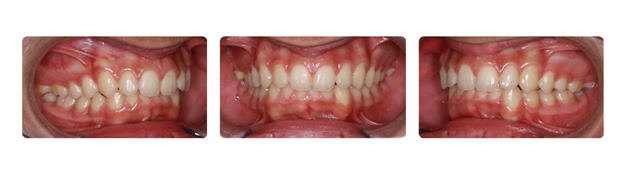

| بعد از قرارگیری دندانها در جای خود ومرتب شدن آنها فک نیز آماده جراحی میباشد: |

![]() |

| پس از جراحی فک وپایان درمان ارتدونسی دندانها و فک به نتیجه مطلوبی رسیده اند: |